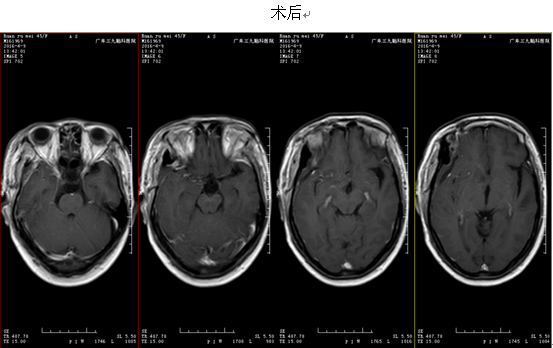

患者因6年前无明显诱因左侧视力下降,无头痛头晕,无恶心呕吐,无四肢抽搐,无发热,遂就诊当地医院,行头颅MR提示颅咽管瘤。予手术治疗(具体不详),术后患者左侧视力失明,术后病理提示:颅咽管瘤。术后患者未行放化疗等进一步治疗。患者于1个月前无明显诱因出现右眼视力下降,无头痛头晕,无恶心呕吐,无四肢抽搐,无发热,随就诊当地医院行头颅MR提示:鞍区占位性病变,颅咽管瘤复发可能性。现患者为求进一步治疗,来我院门诊就诊,门诊拟“颅咽管瘤术后复发”收治入院。患者发病以来,饮食可,睡眠可,大、小便正常。查体:左侧视力消失,右侧视力半米数指,余脑神经体查未见明显异常。辅助检查:我院头颅MR提示:头颅MR提示:鞍区占位性病变,颅咽管瘤复发可能性。入院诊断:颅咽管瘤术后复发;入院后于2016年4月5日行“颅咽管瘤切除术”,术中肿瘤完整切除,术后患者恢复较好,左侧视力同前,未诉头晕、头痛等其它不适。术后病理报告提示:“鞍区”颅咽管瘤(造釉细胞型)。